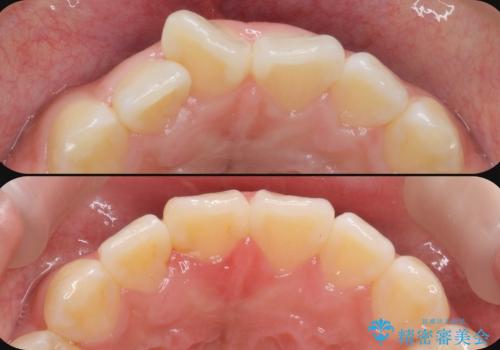

歯のガタガタをマウスピース矯正で治療

- 前歯のガタつきの矯正治療を希望され来院されました。

すでに虫歯で処置がなされている歯が多いこと、歯の磨きやすさに利点があること、装置が見えづらくできることからワイヤー矯正ではなくマウスピース矯正(インビザライン )を用いて歯並びを矯正する計画としました。

もともと虫歯の治療歯が多く歯並びの改善を行い歯を磨きやすくするメリットは大きくありますが、矯正治療中により虫歯が増えてしまう可能性が高いような口腔環境でした。

マウスピース矯正であれば、歯ブラシを行う際にマウスピースをはずして磨くことができるためワイヤー矯正に比べてプラークのコントロールが行いやすいというメリットがあります。

矯正治療を行うにあたり、虫歯を増やさないような治療計画を立てることが重要となります。